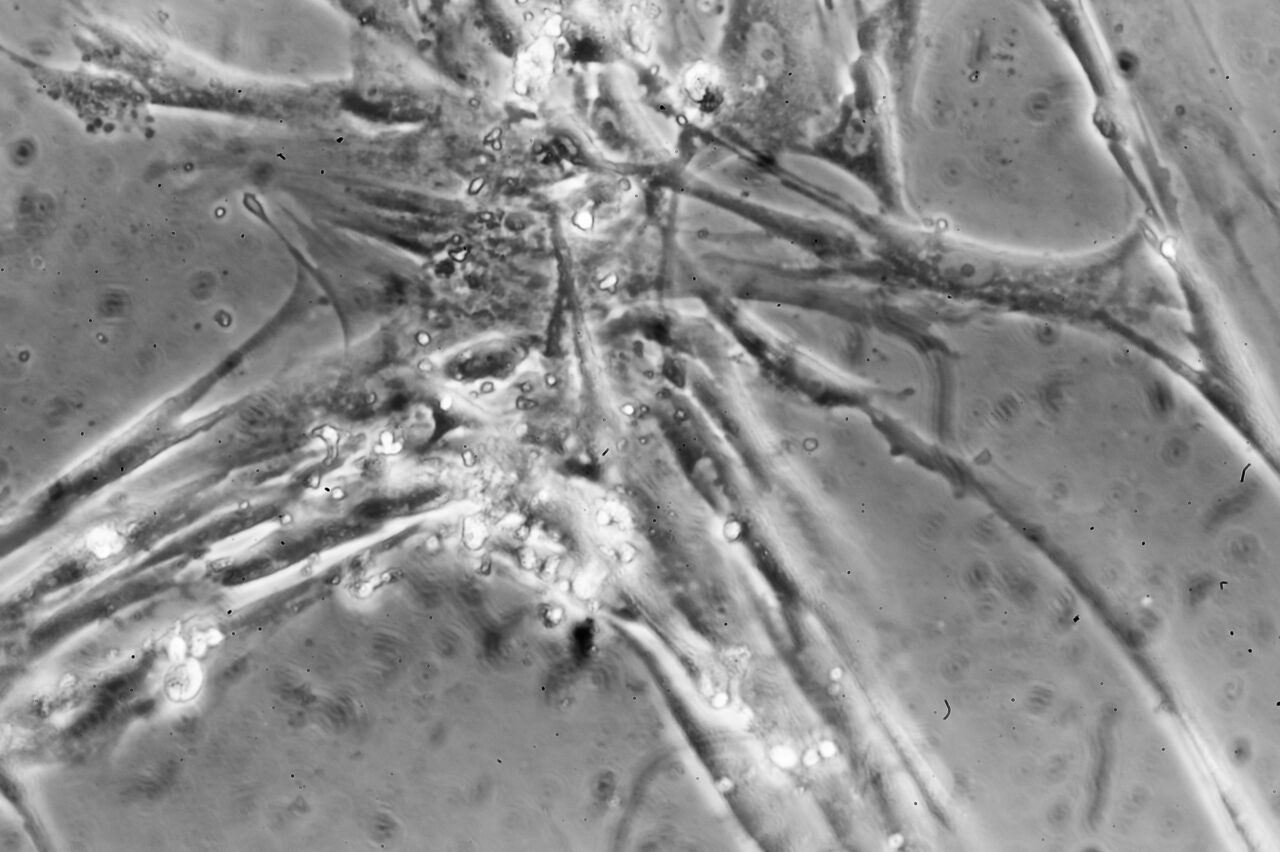

För att ingreppet ska bli lyckat behöver implantatet och benet växa ihop till ett. Forskare i labb.Forskningsingenjör Aneta Liszka jobbar med benceller i Anna Fahlgrens labb. Foto Thor Balkhed Men det är inte så enkelt som det låter även om man skulle kunna tro att läkningen är optimerad av naturen. Hos 1 av 20 patienter lossnar implantatet från benet. Det beror på att benet som protesen fäster i bryts ner av olika anledningar. Det är kostsamt för vården att åtgärda och oerhört smärtsamt för patienten.